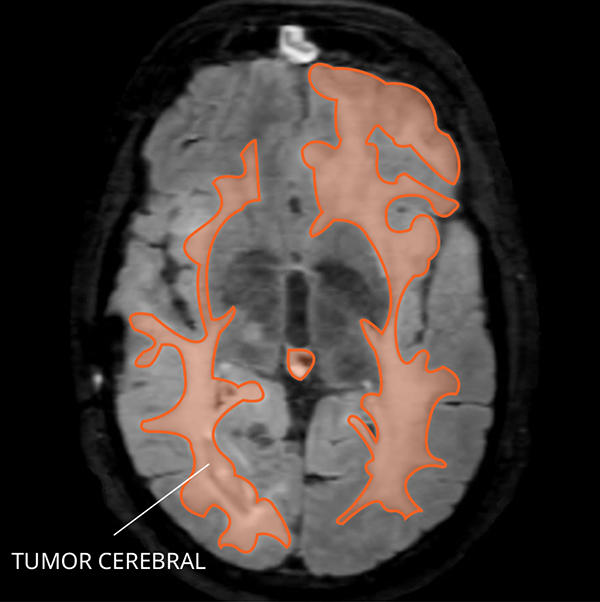

Lista muestra hermosas imágenes de resonancia magnética cerebral normal y anormal dinosenglish.edu.vn para que puedas explorar más en detalle.

resonancia magnética cerebral normal y anormal Pin en NEUROCIENCIAS resonancia magnética de cerebro Resonancia magnética (RM) de cerebro, corte axial ponderado en T2: la … VIDEO Nueva mancha en la Resonancia

Engineer Team : RESONANCIA MAGNETICA Magnetic Resonance Imaging – Clinical Images Hallazgos por resonancia magnética cerebral de nuestro paciente. M, 21 … Imágenes por resonancia magnética anormales como predictoras de mal … Imágenes por resonancia magnética anormales como predictoras de mal … Lesiones en resonancia magnética (RM) del encéfalo y la médula espinal … Pin en Resonancia Magnética del Encéfalo A) Resonancia magnética cerebral (RMC) mostrando infartos en … Caso 1: Edema cerebral visualizado mediante RM. (A) Secuencia T1 plano … Rascacielos dormir pasta tac y resonancia diferencias retrasar … Pin on Apuntes de Enfermería y T.C.A.E Resonancia magnética cerebral secuencia T2, que muestra lesión … Meningitis aguda en la enfermedad de Behçet | Reumatología Clínica Resonancia magnética coronal normal del cerebro Fotografía de stock – Alamy Imágenes de resonancia magnética, la imagen de la cabeza en diferentes … Resonancia magnética cerebral A) protocolo T1 sagital (Caso 1). Se … Resonancia magnética cerebral. Secuencia T1 corte sagital. Atrofia … Resonancia magnética de cerebro, cortes axiales, secuencias T2. Señal … Resonancia magnética de cráneo. A y B) Cortes axiales FLAIR … Resonancia magnética (RM) de cerebro, corte axial ponderado en T2: la … RM cerebral: Interpretación paso a paso | Kenhub Resonancia magnética de cerebro, cortes axiales, secuencias T2. Señal … De Resonancia Magnética De Cerebro Foto de archivo – Imagen de arteria … Top 107+ Imagenes de resonancia cerebral normal – Destinomexico.mx -Imagen por resonancia magnética del cerebro. a) Cortes sagital y axial … resonanCia magnétiCa Cerebral donde se observa hiperintensidad a nivel … MRI (Imagen de resonancia magnética) – Tomografía computarizada de la … Meningioma – NCI Imágenes por resonancia magnética coloreadas del cerebro sano del … Resonancia magnética cerebral en secuencia FLAIR, que muestra lesiones … Contraste resonancia magnetica cerebral – senturinthegreen Relación de los espacios de Virchow-Robin con la enfermedad de … Gliomatosis cerebral – Instituto Nacional del Cáncer Pin en Neurology. Recomendaciones para la utilización e interpretación de los estudios de … Fotografía De La Proyección De Imagen De Resonancia Magnética Del … atmósfera Dirigir Cumplir anatomia resonancia magnetica Desarrollar … Pin en #MEDICINA,#SALUD Resonancia magnética de la nasofaringe De Resonancia Magnética De Cerebro Foto de archivo – Imagen de polilla … Atrofia cortical global de predominio parietal en la Resonancia … Resonancia magnética cerebral | Download Scientific Diagram Neuroblog: Resonancia magnética cerebral en la trombosis crónica de … De Resonancia Magnética De Cerebro Imagen de archivo – Imagen de … ¿Cuáles son los riesgos de la resonancia magnética? – Integra Salud … Resonancia magnética cerebral al decimocuarto día de ingreso: área … Resonancia magnética. Corte axial mostrando área infartada en el … Resonancia magnética cerebral del paciente AV evidenciando lesiones en … -Ressonância magnética de encéfalo mostrando múltiplas imagens … Resonancia magnética cerebral secuencia FLAIR (Fluid Attenuated … Resonancia magnética cerebral con protocolo de epilepsia, en sección … Resonancia magnética cerebral en corte sagital. Se observa una evidente … Resonancia magnética craneal en la que se evidencian lesiones … Logran visualizar el cerebro a detalle más completo tras una resonancia … Así decide el cerebro la severidad de un castigo De Resonancia Magnética De Cerebro, Imagen de archivo – Imagen de … A) Resonancia magnética cerebral; Secuencia Tof: oclusión de arteria … Un estudio asocia la ansiedad con la aparición rápida del Alzheimer IMÁGENES DE 18 F-PR04.MZ PET FUSIONADA CON RESONANCIA MAGNÉTICA … Imágenes por resonancia magnética anormales como predictoras de mal … Tumores de la región pineal – Instituto Nacional del Cáncer Epilepsia: una historia de voces y fantasmas | Neurología Contribución de las imágenes de resonancia magnética por tensor de … Resonancia magnética secuencia T2 plano coronal de quiste epidermoide … Resonancia Magnética Cerebral del paciente: a. Aumento de… | Download … Resonancia magnética cerebral 2022 Síndrome de hemiconvulsión-hemiplejía-epilepsia. Seguimiento de un caso … Enfoque Radiologico: La resonancia magnética permite detectar lesiones … Resonancia magnética craneal T1 con contraste que muestra angiomatosis … guidewiz – Blog Resonancia magnética cerebral, secuencia SWI. Ribete hipointenso en la … resonAnCiA mAgnétiCA de ColumnA Con gAdolinio. Corte sAgitAl en t1 de … SEMANA 12: FUNDAMENTOS DE RESONANCIA MAGNÉTICA NUCLEAR. INDICACIONES Y … DIAGNÓSTICO DE ESCLEROSIS MÚLTIP Magnetic resonance imaging of the brain – Alchetron, the free social … Resonancia magnética de órbitas | Instituto Radiológico Dr. E Castillo Alteración de la marcha en un paciente post-trasplante hepático Resonancia magnética cerebral de un paciente sano (Ay B) y paciente que … Utilidad de la resonancia magnética craneal para el diagnóstico de la … Resonancia Magnética Del Cerebro El Tumor Cerebral Foto de stock y más … De Resonancia Magnética De Cerebro Imagen de archivo – Imagen de … ABDALLA RADIOLOGIA: NEURINOMA ACUSTICO Atrofia cortical global de predominio parietal en la Resonancia … Resonancia Magnética : Producción de la imagen MRI Brain Scan — Stock Photo © Bunyos30 #18724051 Mri (imagen de resonancia magnética) Monitor con imagen de captura de … Tomografía computarizada vs resonancia magnética: diferencia y … Tumores Cerebrales – Unidad de Neurocirugía RGS Resonancia magnética de la columna, sección sagital. Observe los discos … La resonancia magnética, una técnica imprescindible en el diagnóstico … Perfusión Cerebral por Resonancia Magnética | ¿Qué es? ¿Necesita Contraste? Resonancia Magnética Cerebro A: resonancia magnética, T2 coronal preoperatoria; se observa lesión en … Resonancia magnética cerebral — Foto de stock © Bunyos30 #27340623 La resonancia magnética se perfila como detector de mentiras | Futuro … Resonancia magnética cerebral en T1 con gadolinio, cortes axial (a … MRI brain : show brain tumor at right parietal lobe of cerebrum — Stock … NEUROIMÁGENES EN ENFERMEDAD DE PARKINSON: ROL DE LA RESONANCIA …